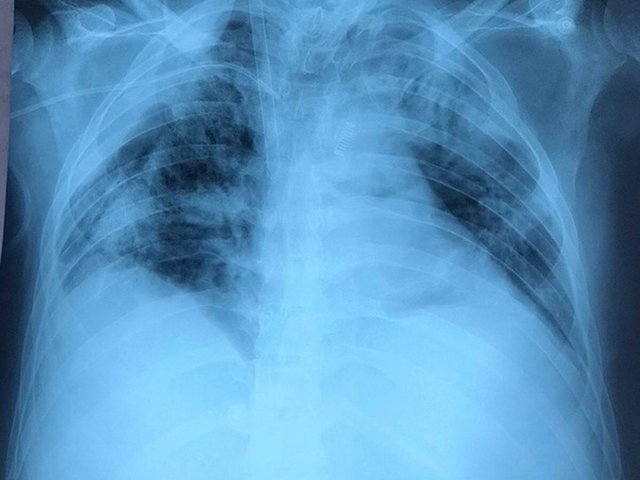

Bệnh nhân phi công tập tự thở bằng phổi

Phổi "bệnh nhân 91" cải thiện khá hơn, bác sĩ Bệnh viện Bệnh Nhiệt đới TP HCM đang giảm dần các thông số...